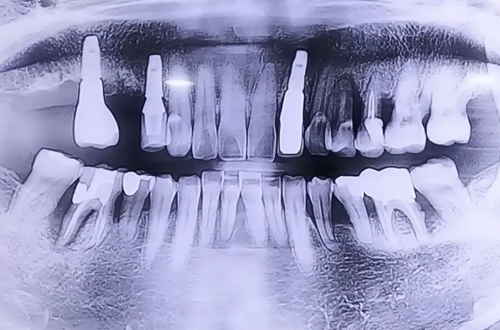

기존 임플란트 사이 공간에 새로운 임플란트를 심은 사례

치료 유형 기존 임플란트 사이 공간에 새로운 임플란트 식립

주로 왼쪽으로만 식사하시면서 심한 염증들로 인해 치아가 많이 약해져 통증을 호소하시며 방문하신 환자분이십니다.

잇몸 치료와 약 복용으로 염증은 많이 호전된 상태이며 오른쪽으로 음식물을 씹을 수 있도록 기존 임플란트 사이 공간에 작은 어금니 하나 큰 어금니 하나씩 임플란트를 진행해 드렸습니다.

오른쪽 위 임플란트가 회복되시면 왼쪽 위아래 임플란트를 진행할 계획입니다.

임플란트와 주변 뼈들이 단단하게 굳는 기간인 4개월을 기다린 후 임플란트 위쪽 머리 부분들을 제작해 드릴 예정입니다.